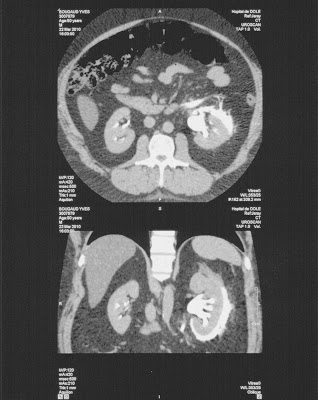

Fornix ruptura vesekő talaján Szerző: admin | febr 10, 2011 | Forniceal rupture, Kidney stones | Nincsenek hozzászólások natív és kontrasztanyagos mérésen a vese körül folyadéksáv látszik késői fázisban (7 perc) a kontrasztanyag a vesekontúr mellett keskeny sávban megjelenik (fornix ruptura) scannelt képekUH vizsgálattal felfedezett ureterolithiasis